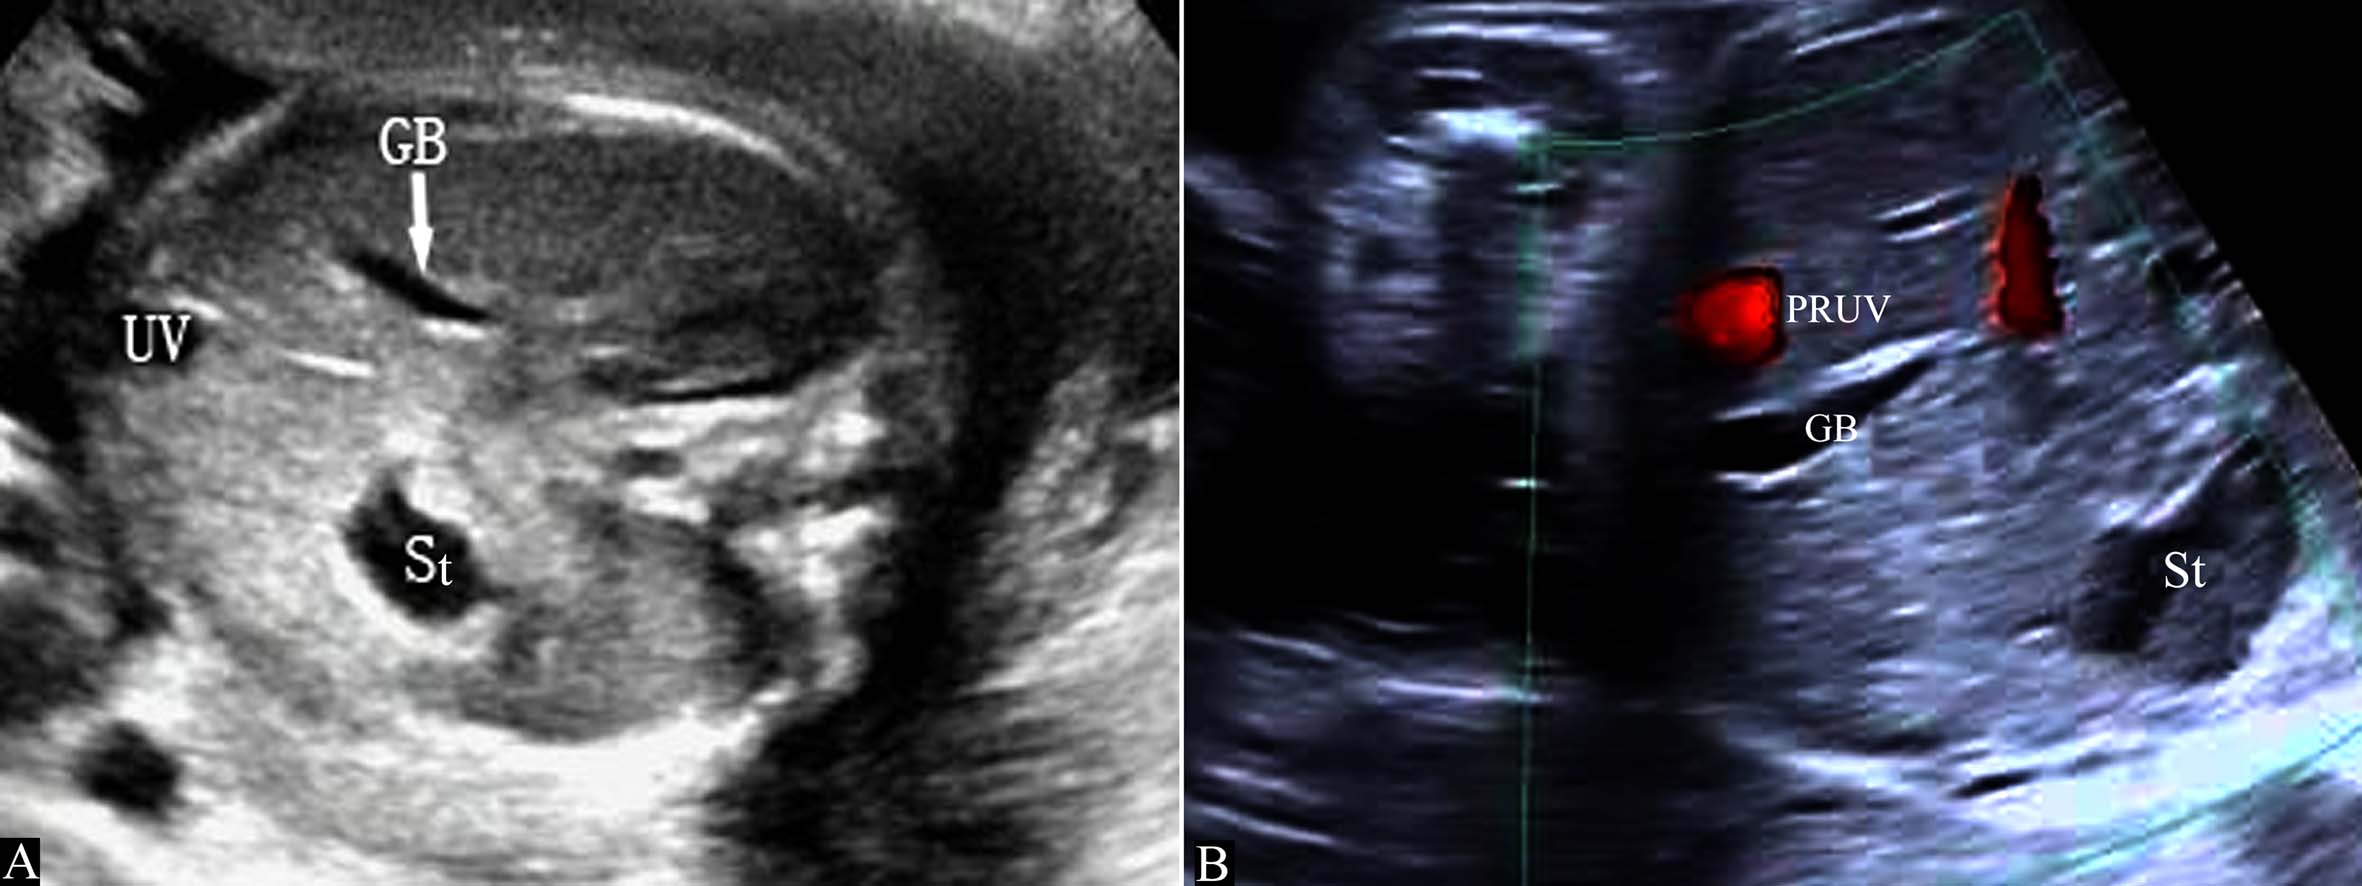

胚胎4周末右脐静脉开始闭锁,第7周时消失,形成正常的左脐静脉循环(图7A)。如右脐静脉不闭锁退化而左脐静脉闭锁,右脐静脉经过肝脏与静脉导管相连进入静脉导管,或绕过肝脏直接与下腔静脉或右心房相连(图7B),形成持续性右脐静脉7。在Hill等1994年进行的回顾性分析中,在15237例产科超声检查中发现了33例PRUV,产前超声检查显示率为0.21%(1:476);其中有18.2%(6/33)的伴有严重的先天性发育异常;在另一篇研究报道中,研究者在低风险胎儿中发现PRUV为1:526,其中17例胎儿合并其他部位的畸形,包括无脑儿、复杂性心脏畸形、双侧唇裂、孤立肾、单脐动脉等。

胎儿腹部横切面显示胃泡和脐静脉以后观察胆囊的位置可以确定脐静脉走行。正常脐静脉穿过脐轮后走行于胆囊的左侧,在胆囊与胃腔之间可以显示脐静脉的回声(图8A);如果在胆囊右侧显示脐静脉回声即可明确右脐静脉的诊断((图8B));肝内型持续性右脐静脉进入肝脏后PRUV需要转向左侧与静脉导管连接(图9)。连续追踪扫查如果显示脐静脉周围或一侧无肝脏实质,则提示为肝外型持续性右脐静脉。一般认为,后者常合并其他部位的发育异常,并可以合并染色体异常。

图8 正常脐静脉与持续性右脐静脉声像图比较

图11-54 持续性右脐静脉声像图